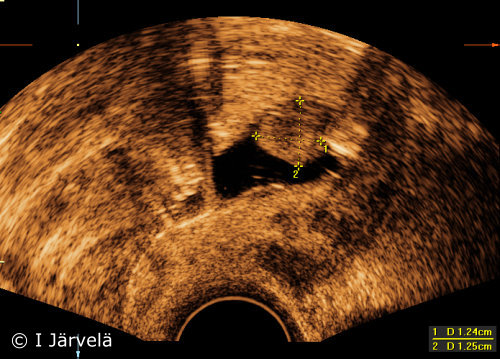

Endometrial Polyp (Sonohysterography)

Endometrial polyp (sonohysterography). Endometrial polyp in sonohysterography

Picture: Ilkka Järvelä; text: Dimitrios Scordas